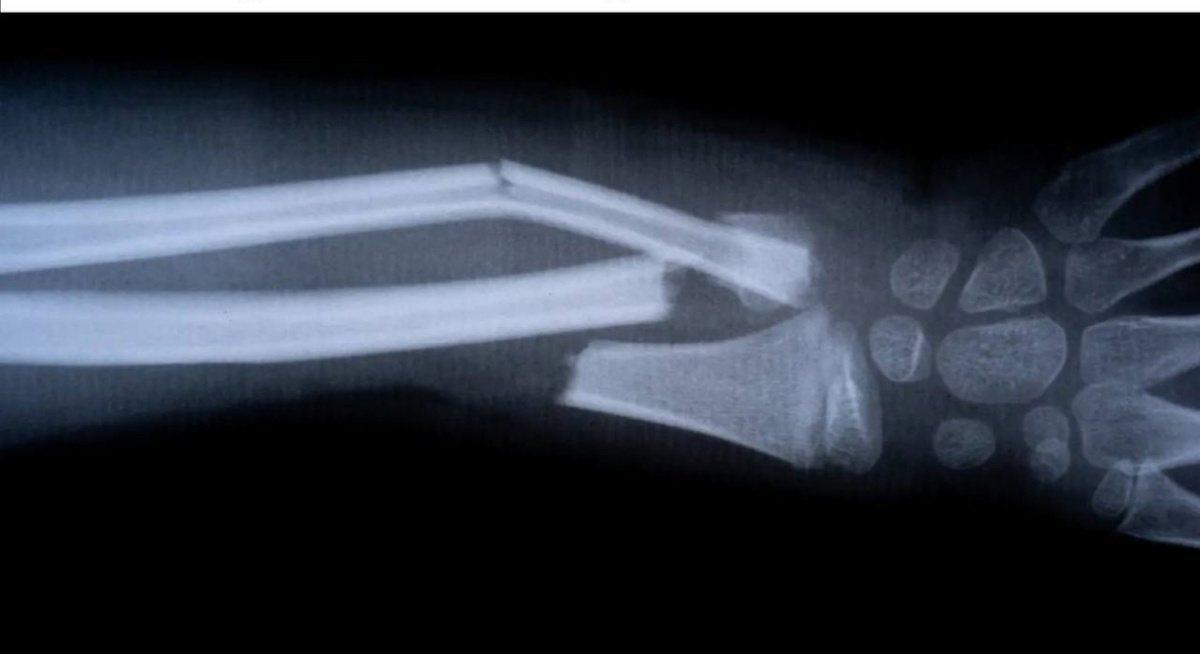

В мире медицины, где лечение сложных переломов часто напоминает работу ювелира с долотом и молотком, новость из Китая прозвучала как фантастика. Биоинженеры представили материал под названием «Bone-02» — инъекционный клей, который, по утверждениям, способен за несколько минут скрепить сломанные кости, работая даже в условиях кровотечения и не боясь влаги. Если эти заявления подтвердятся в широкой клинической практике, нас ждет одна из самых значимых ортопедических революций за последние десятилетия. Проблема: Битва с переломом — почему традиционные методы неидеальны Чтобы понять масштаб потенциального прорыва, нужно осознать недостатки современных подходов к лечению сложных переломов, особенно оскольчатых, когда кость раздроблена на несколько фрагментов. 1. Остеосинтез с металлоконструкциями: Это золотой стандарт сегодня. Хирурги используют титановые пластины, винты, спицы и стержни, чтобы механически собрать кость воедино.   · Риски: Любая операция — это риск инфицирования, крово

В мире медицины, где лечение сложных переломов часто напоминает работу ювелира с долотом и молотком, новость из Китая прозвучала как фантастика. Биоинженеры представили материал под названием «Bone-02» — инъекционный клей, который, по утверждениям, способен за несколько минут скрепить сломанные кости, работая даже в условиях кровотечения и не боясь влаги. Если эти заявления подтвердятся в широкой клинической практике, нас ждет одна из самых значимых ортопедических революций за последние десятилетия.

Чтобы понять масштаб потенциального прорыва, нужно осознать недостатки современных подходов к лечению сложных переломов, особенно оскольчатых, когда кость раздроблена на несколько фрагментов.

1. Остеосинтез с металлоконструкциями: Это золотой стандарт сегодня. Хирурги используют титановые пластины, винты, спицы и стержни, чтобы механически собрать кость воедино.